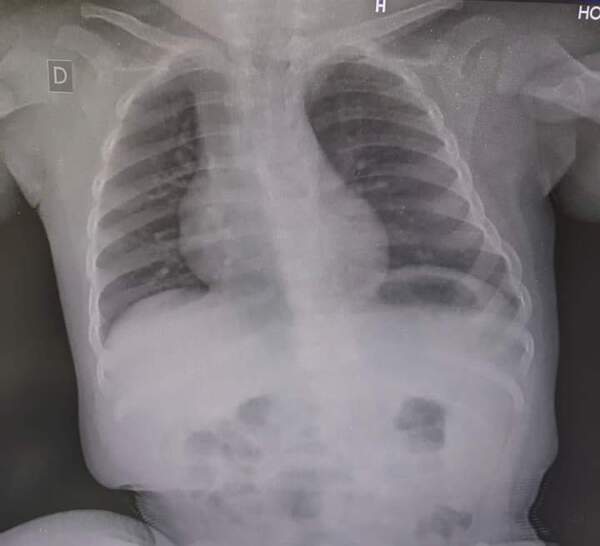

Un menor de un año oriundo del distrito de Pirapó fue trasladado hasta el Hospital Regional de Encarnación con dificultad respiratoria y tos. Luego de ser sometido a evaluaciones por imágenes, se detectó que el problema fue por un maní con el cual se atragantó. ...[Leer más]